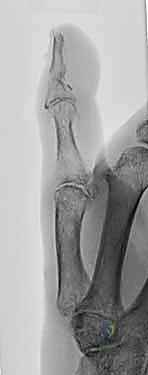

الأساس المتين هو أول خطوة في البناء. يقوم الدكتور هطيف بتقصير العظام قليلاً (Bone Shortening) لتخفيف الشد على الأوعية الدموية والأعصاب عند توصيلها. يتم تثبيت العظام باستخدام أسلاك كيرشنر المعدنية (K-wires)، أو مسامير دقيقة، أو صفائح معدنية صغيرة. التثبيت يجب أن يكون قوياً ليسمح ببدء العلاج الطبيعي المبكر.